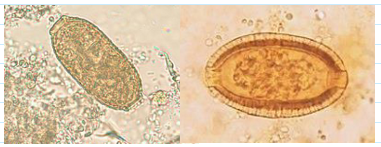

capillaria philippinensis eggs

Must not confuse with Trichuris eggs

35-45 x 20-25 um

More squarish than Trichuris eggs

Less conspicuous polar plugs

Flatter and less prominent

Thick striated shell